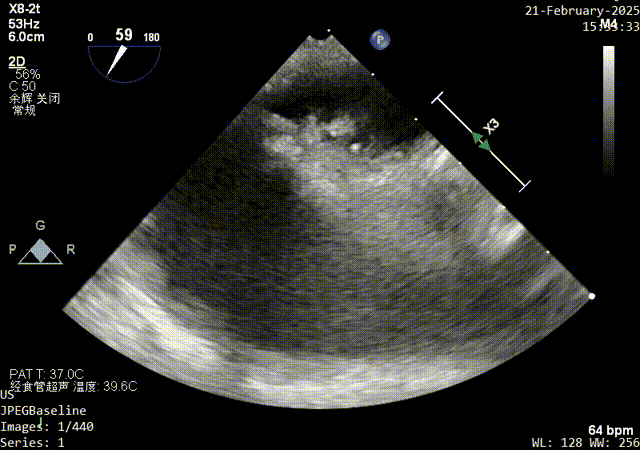

color超声影像

1、PFO结构:巨大型PFO,静息状态下房水平左向右分流。继发隔厚约5.7mm;原发隔厚约1.2mm;未见明确下腔静脉瓣及希阿里网回声。

2、PFO参数:隧道裂隙宽约4.4mm ;卵圆孔隧道长度14mm;